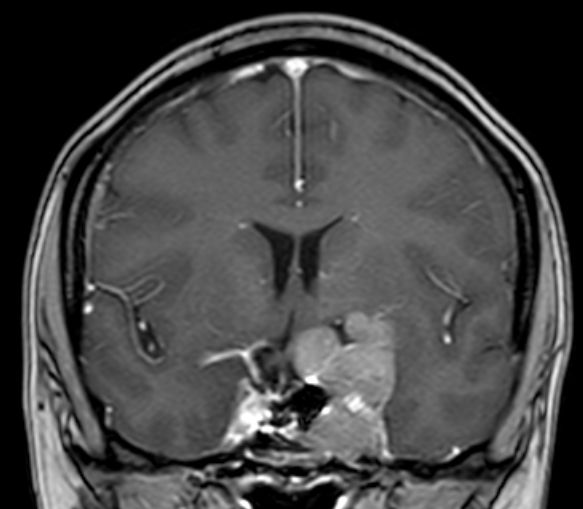

| Adenom | 42-jährige Krankenpflegerin mit

atypischem Hypophysenadenom. Z.n. transsphenoidaler Resektion. Hemianopsie

rechts. Großer extrasellärer Anteil. Ummauerung der Arteria carotis interna

links. Größe 4,2 x 4,2 x 2,7 cm überwiegend links der Mittellinie,

größenregredient, Ränder sind glatt begrenzt, die Kontrastmittelaufnahme

homogen. Ausdehnung vom Orbitatrichter in die Sella und nach dorsorostral bis

zum Hirnstamm und die Temporalgrube.![]() | ||||